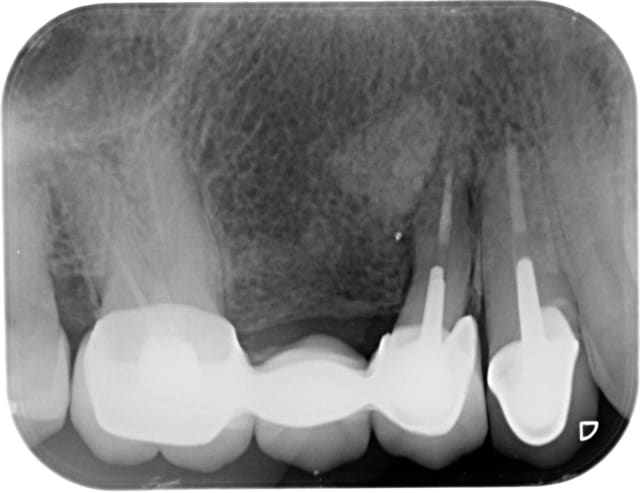

Patiente 79 ans.

gène au niveau de la gencive. a été traité par ATBthérapie à Paris pour cette "spicule".

A l'inspection, j'ai une exostose et un petite fistule sans suppuration, un peu plus distale.

La radio montre une belle masse radio-opaque homogène.

un traitement endo qui semble avoir omis un canal.

Qu'est ce donc selon vous ?

Sur la radio ça ressemble un peu à un apex je trouve, pas toi?

De même, ça ressemble plus à un apex résiduel qu'à une exostose, ce qui explique l'infection chronique en rapport (complication infectieuse sur exostose?)

PENSE AUSSI a un apex...

Apex aussi....

Je veux pas dire mais l'image radio-opaque on en a rien à cirer ici puisque c'est la prémolaire qui est morte avec une belle lésion apicale.

à extraire.

Ha oui merci, je le vois aussi maintenant